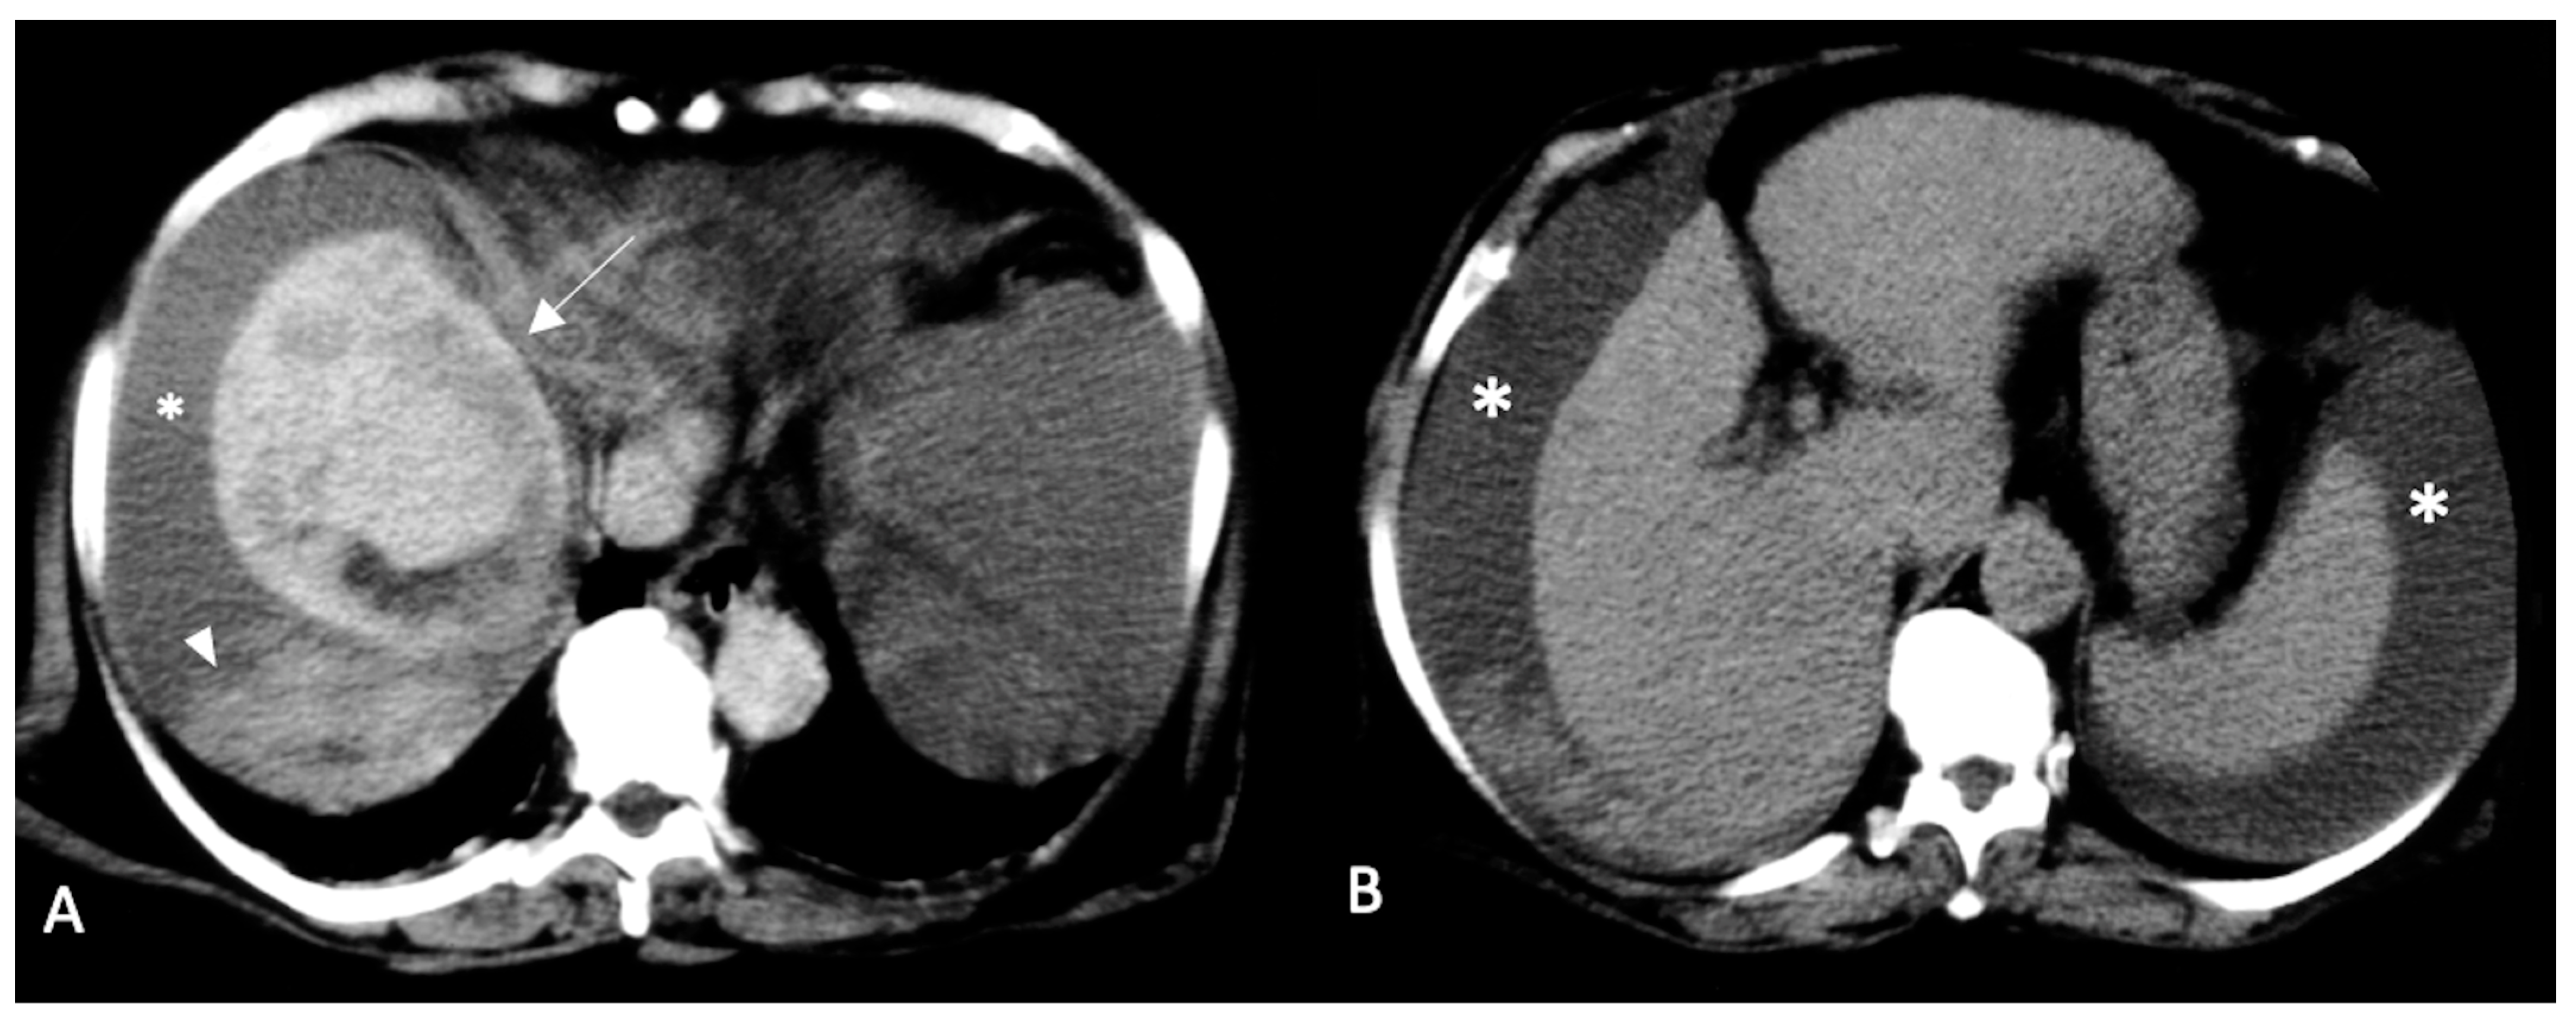

- Kim, H.C.; Yang, D.M.; Jin, W.; Park, S.J. The Various Manifestations of Ruptured Hepatocellular Carcinoma: CT Imaging Findings. Abdom. Imaging 2008, 33, 633–642. [Google Scholar] [CrossRef]

- Singhal, M.; Sinha, U.; Kalra, N.; Duseja, A.; Khandelwal, N. Enucleation Sign: A Computed Tomographic Appearance of Ruptured Hepatocellular Carcinoma. J. Clin. Exp. Hepatol. 2016, 6, 335–336. [Google Scholar] [CrossRef]

- Casillas, V.J.; Amendola, M.A.; Gascue, A.; Pinnar, N.; Levi, J.U.; Perez, J.M. Imaging of Nontraumatic Hemorrhagic Hepatic Lesions. RadioGraphics 2000, 20, 367–378. [Google Scholar] [CrossRef]

- Tsitouridis, I.; Michaelides, M.; Christopoulou, A.; Sidiropoulos, D.; Kyriakou, V.; Diamantopoulou, A.; Bintoudi, A. Early Stage of Intraperitoneal Rupture of Hepatocellular Carcinoma: CT and MRI Evaluation. Ann. Gastroenterol. 2007, 20, 282–285. [Google Scholar]